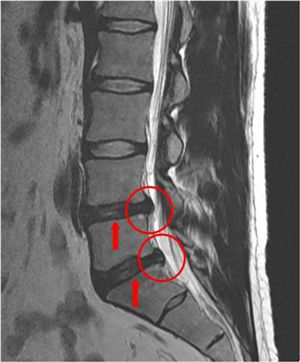

살면서 허리 한번 안 아파 본 사람이 없을 정도로 허리통증은 누구나 한번쯤 경험하는 흔한 증상이 됐다. 흔하다보니 '괜찮아지겠지'하고 방치하는 경우가 많은데, 늑장치료는 더 큰 문제를 만들 수 잇다. 이에 대해 자생한방병원 척추디스크센터 김정철 원장과 알아보도록 하자. 허리통증이 처음 생겼을 때 바로 치료를 받으면 간단한 문제로 끝날 수 있지만 방치했을 때는 허리디스크에 척추관협착증까지 혹은 허리디스크에 목디스크까지 생기는 이른바 두 가지 이상의 복합 척추질환이 야기될 수 있다. 때문에 한 가지 질환만 있을 때보다 통증도 심해지게 되고, 치료기간 또한 길어질 뿐 아니라 비용도 더 많이 들게 된다.이런 도미노 현상은 생기는 걸까. 척추는 24개의 뼈가 유기적으로 연결되어 있는 구조다. 여기서 한 부분의 디스크가 터질 경우 이 디스크가 해야 될 역할을 주변에 있는 다른 부분이 대신해줘야 한다. 결국 다른 디스크에까지 무리가 가게 돼 주변 근육이나 인대 등이 약해져 또 다른 질환이 발생하게 되는 것이다.그 중에서도 복수로 많이 나타나는 경우가 허리디스크와 퇴행성디스크를 가지고 있는 경우다. 허리뼈 사이에 있는 디스크가 밀려나와 신경을 눌러 발생한 질환이 허리디스크, 뼈와 디스크가 노화되면서 뼈에서 칼슘이 빠져나가고 디스크에서 수분이 빠져나가 납작해지면서 검게 변성되는 것이 퇴행성디스크다. MRI 사진에서 보이는 바와 같이 동그라미 부분이 디스크가 탈출된 부분이다. 이 부분의 디스크가 탈출되면서 화살표로 표시되어 있는 디스크에까지 영향을 받게 되고, 디스크의 수분이 빠져나가 검게 변성되고 납작해지면서 퇴행성디스크를 유발하게 되는 것이다. 이렇게 허리디스크와 퇴행성디스크가 동시에 나타날 경우 허리통증과 함께 다리가 저리고 시리며 아픈 증상이 나타난다.그렇다면 복합질환은 어떻게 치료해야 할까. 척추질환을 치료하는 데 있어 가장 중요한 것은 척추질환의 근본 원인인 약해진 척추와 주변 조직을 튼튼하게 하여 재발을 방지하는 것이다. 그러므로 약해진 척추뼈와 디스크, 주변의 근육과 인대를 튼튼하게 해주고 비뚤어진 척추를 바로 잡아주는 치료를 해야 한다. 두 가지 이상 척추질환이 있는 환자들은 대부분 오랜시간 동안 통증으로 인해 몸도 마음도 약해져 있기 쉽다. 그러므로 추나약물치료를 우선적으로 실시하여 체력을 보강해가며 치료를 진행하는 것이 좋다. 자생한방병원은 과학적으로 입증된 치료법으로 척추질환을 치료하고 있다. 수술없이 척추질환을 치료하는 자생 치료법에는 추나수기치료, 추나약물치료, 특수침치료가 있다. 추나수기치료는 척추 이상에 대한 근원적인 치료로 비뚤어진 척추 뼈를 바로 잡아주고 긴장된 근육을 이완시켜 통증을 줄어준다. 뼈와 관절이 비정상적으로 틀어지게 되면 뼈를 지지하고 있는 근육과 인대가 긴장하고 뭉쳐서 혈액순환이 원활하지 못해 통증이 발생하게 된다. 이때 한의사가 손을 이용하여 틀어진 척추와 관절의 위치를 바로 잡아주고 몸 전체의 기혈 순환을 원활하게 하는 추나수기요법으로 통증을 제거할 수 있다. 한약을 통한 추나약물은 동의보감에서 뼈와 근육을 보한다고 쓰인 약재를 중심으로 증상별 처방을 하게 된다. 추나약물은 퇴행되고 부어 있는 디스크를 가라앉혀 주고 디스크와 척추 주변의 인대와 근육을 강화시켜 주는 효과가 있다. 또한 척추뼈 자체를 튼튼하게 해 추후에 디스크가 재발하고 척추와 골반이 다시 틀어지는 것을 막아주기도 한다.'한방으로 척추질환이 치료가 될까'는 의구심을 가지고 있는 사람들이 있다. 하지만 추나약물의 효과는 이미 과학적으로 수 차례 입증된 사실이다. 자생한방병원이 서울대 천연물과학연구소, 성균관대학교 약대 등과 공동으로 추나약물의 성분으로 실험한 결과, 염증 제거 및 신경재생 효과가 뛰어나다는 사실이 입증되었다. 또한 골세포가 정상으로 환원되는 뼈 재생 효과와 손상된 연골이 회복되는 데 탁월한 효과가 있음이 확인됐다.척추질환을 치료하는데 있어 봉침과 약침요법의 효과도 크다. 봉침요법은 자연 상태의 벌이 가지고 있는 독을 추출하여 인체에 무해하도록 정제한 봉독을 사용하는 치료법으로, 척추디스크로 인한 통증과 염증을 완화시키는 효과가 있다. 약침요법은 녹용, 인삼, 홍화 등 순수 한약재의 유효성분을 추출해 경혈과 통증 부위에 주입하는 치료로, 침과 한약의 효과를 동시에 볼 수 있고 혈액순환을 좋게 하여 통증을 가라앉혀 주는 효과가 있다.늑장치료로 인해 발생할 수 있는 척추질환 도미노 현상에 대해 살펴봤다. 옛말에 호미로 막을 거 가래로 막는다는 말처럼 허리에 통증이 있고 불편하다고 느껴진다면 대수롭지 않게 생각하지 말고 빨리 척추전문병원을 찾아 정확하게 병을 진단하고 치료해야 할 것이다.<위 내용은 아시아경제신문의 편집 방향과 무관하며 해당 업체에서 제공한 보도자료입니다.><ⓒ세계를 보는 창 경제를 보는 눈, 아시아경제(www.asiae.co.kr) 무단전재 배포금지>